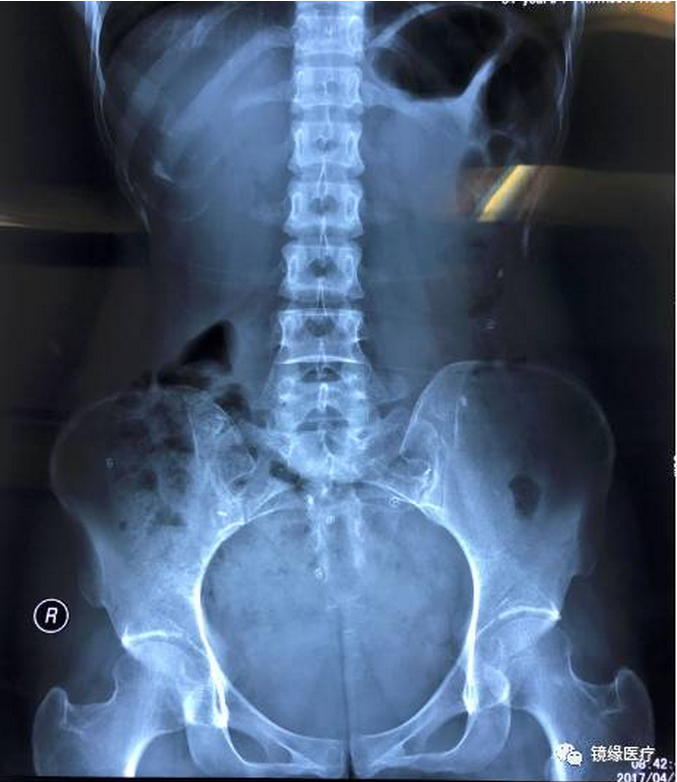

检查当天,吞服一颗O环型胶囊;24h后吞服第二颗双D型胶囊;48h后吞服第三颗三室型胶囊。于吞服第一颗胶囊72h后拍摄一张腹部平片。

如图所示:患者第一天服用的O环形标记物以及第二天服用的双D型标记物均已全部排出体外,也就是说患者72h以及48h标记物排出率均为100%,由此我们可以得出该患者的结肠传输功能是正常的。